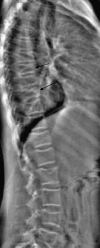

This article reviews dual X-ray absorptiometry (DXA) technique and interpretation with emphasis on the considerations unique to pediatrics. Specifically, the use of DXA in children requires the radiologist to be a "clinical pathologist" monitoring the technical aspects of the DXA acquisition, a "statistician" knowledgeable in the concepts of Z-scores and least significant changes, and a "bone specialist" providing the referring clinician a meaningful context for the numeric result generated by DXA. The patient factors that most significantly influence bone mineral density are discussed and are reviewed with respect to available normative databases. The effects the growing skeleton has on the DXA result are also presented. Most important, the need for the radiologist to be actively involved in the technical and interpretive aspects of DXA is stressed. Finally, the diagnosis of osteoporosis should not be made on DXA results alone but should take into account other patient factors.